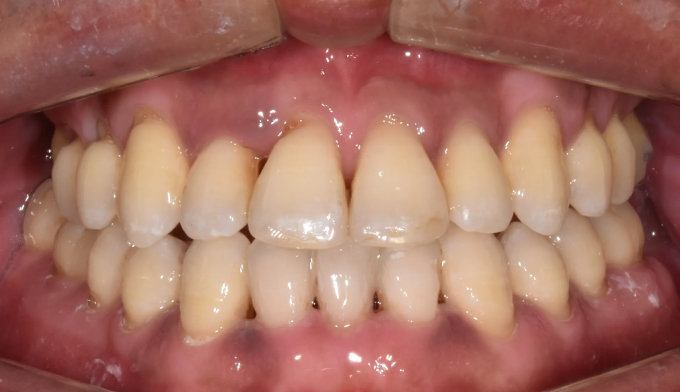

그동안 구강관리 소홀로 아래앞니 하나가 충치로 인해 소실되었으며, 동시에 골격의 주걱턱 경향으로 인해 앞니가 거꾸로 물리는 상황입니다. 아래앞니 빈공간을 임플란트나 크라운과같은 보철치료로 마무리 할 수도 있지만 교정치료를 통해 공간을 메운다면 동시에 거꾸로 물리는 앞니도 개선 가능하므로 교정치료가 보철치료보다 훨씬 효과적인 치료라고 볼 수 있습니다. 환자분의 교정치료에 대한 협조도와 이해도가 높아 비교적 이른 시간내에 교정치료가 마무리되어 매우 만족해 하셨던 케이스입니다. 총 교정기간은 14개월 소요되었습니다.